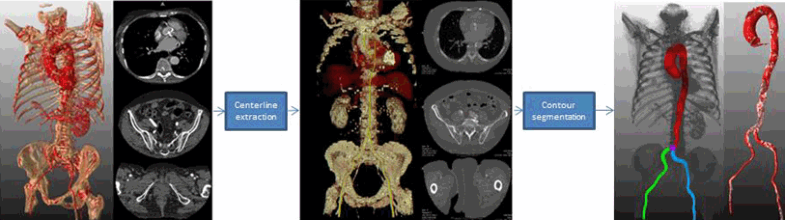

The approach that we have taken consists of two steps (Fig. 1), firstly, a centerline extraction from the femoral arteries to the aortic root [11]; and secondly, a 3D contour detection approach using a subdivision surface model fitting method to accurately delineate the vascular access route [10]. Validation of this study was realized on 36 CTA datasets which were acquired during routine clinical practice prior to the TAVR procedures.

The general pipeline of trajectory contour detection, including two steps: centerline extraction and contour detection